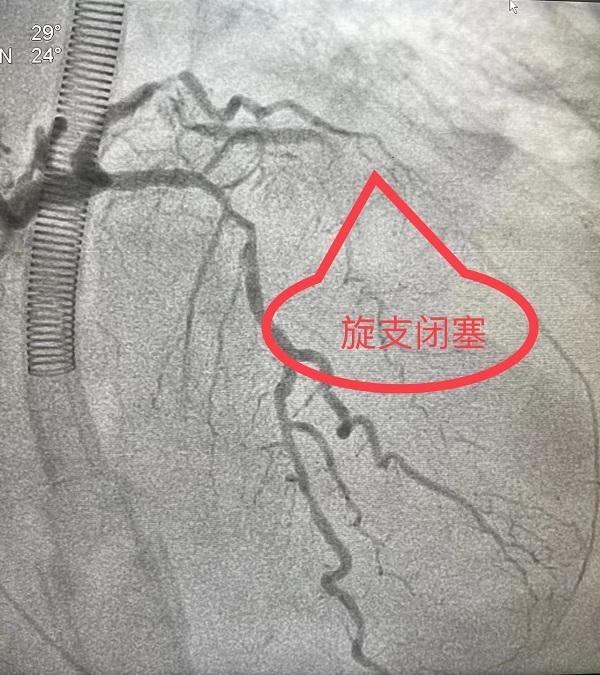

7月11日,潘女士在陕健医二一五医院胸外科进行腔镜下胸腺瘤手术,经过术后10天的恢复,7月21日8时,潘女士准备出院,而就在此时,潘女士突发意识丧失,呼吸心跳骤停,胸外科薛锋主任立即组织抢救,心电监护提示心室颤动,一场与死神赛跑的战斗展开,心肺复苏、电除颤、气管插管、呼吸机辅助呼吸……生命体征恢复,医院心内一科刘二伟主治医师急会诊,行心电图检查见Ⅰ、aVL、V4-V6导联ST段抬高型0.1mV–0.3mV,考虑急性ST段抬高型心肌梗死,刘积伦主任医师在气管插管下急诊行冠脉造影术,冠脉造影提示左旋支中段100%闭塞,急诊行冠脉支架植入术,顺利开通了急性闭塞的冠脉。术后,经过医生和护士精心治疗和护理,患者恢复良好,顺利康复出院。